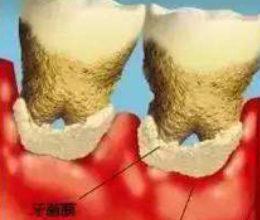

破壞牙齒完整性

造成牙槽骨萎縮

咀嚼功能(néng)減退

食物(wù)嵌塞牙齒松動

牙齒缺損

牙齒缺失

齲 齒